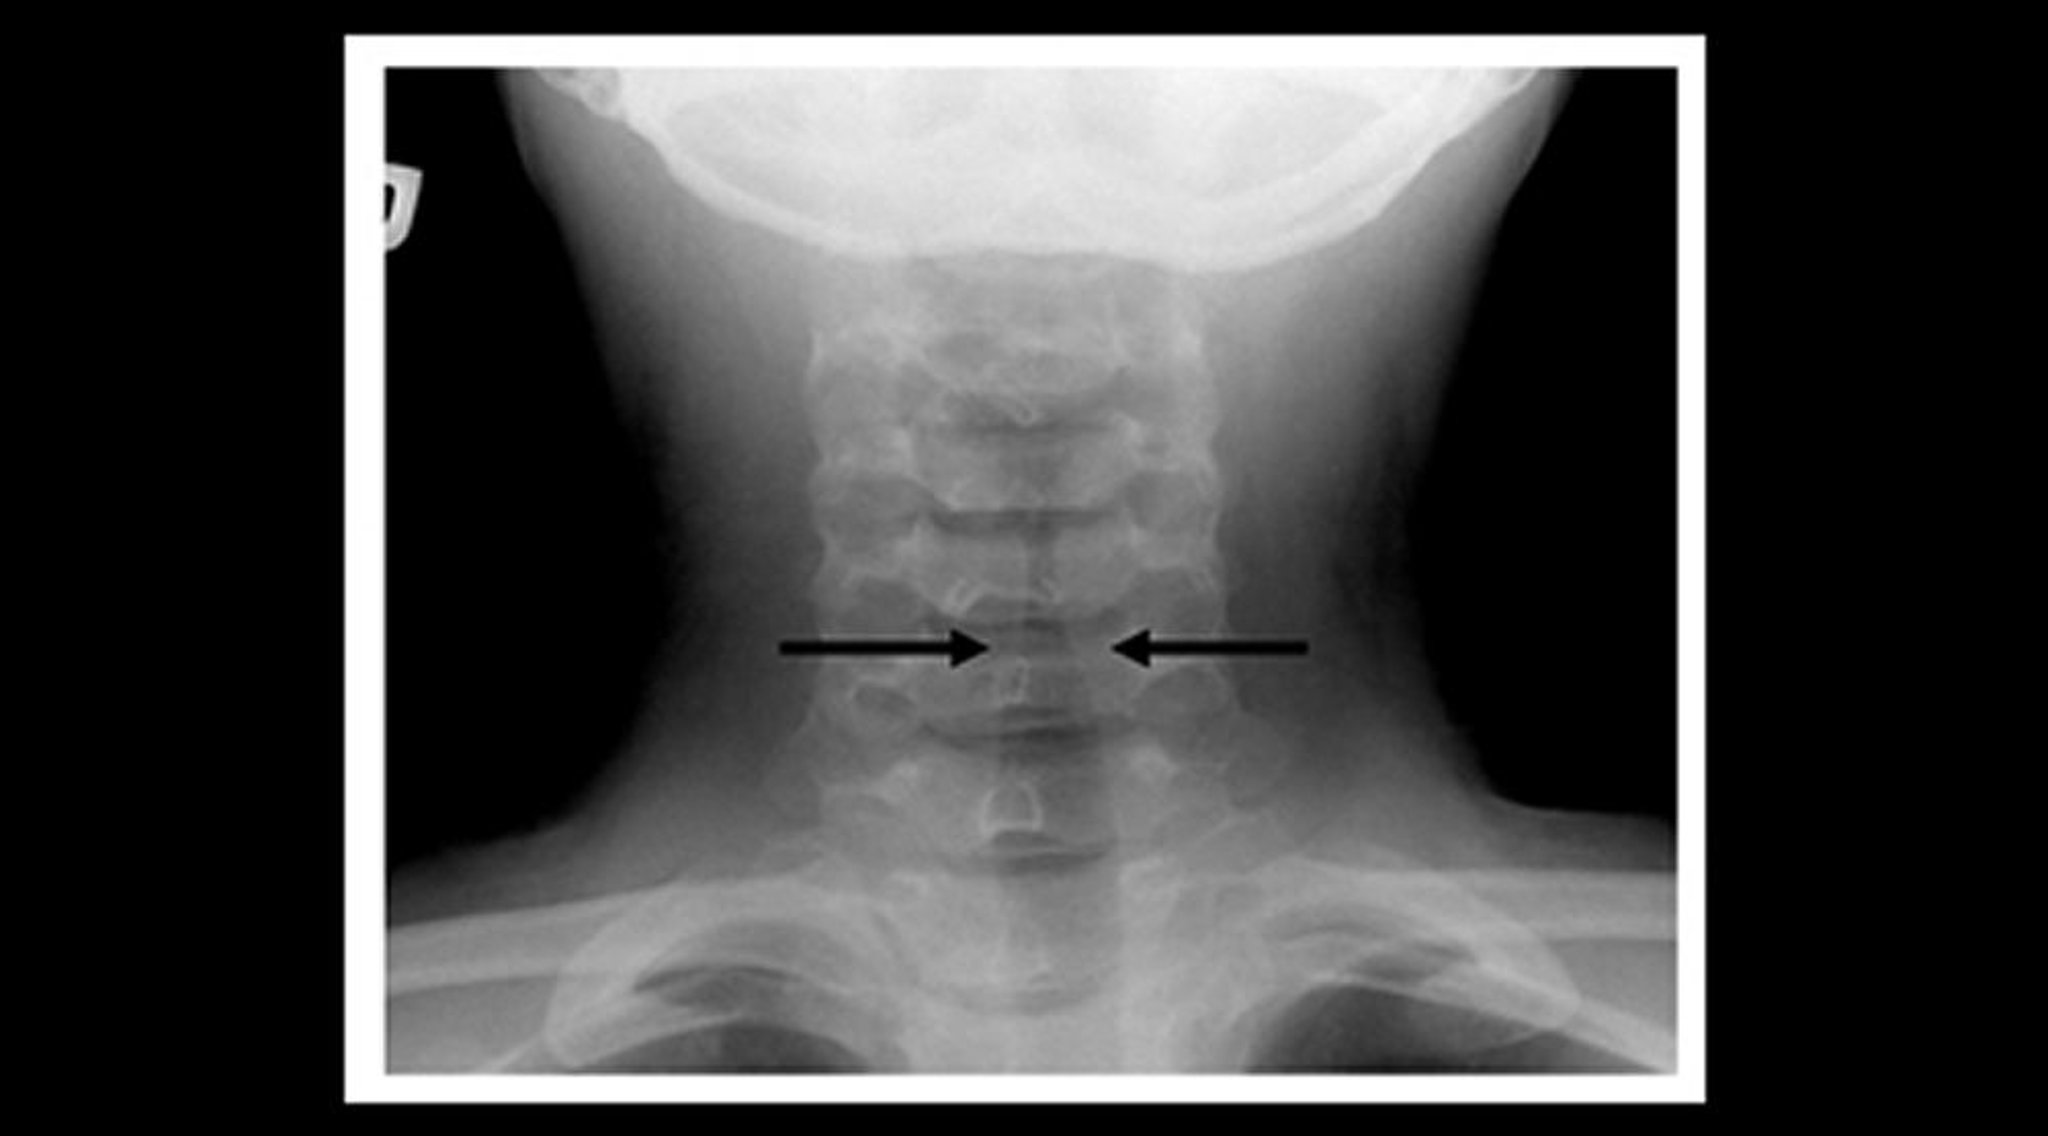

Radiographie d'un enfant atteint de laryngite striduleuse (vue coronale)

Les radiographies du cou des tissus mous d'un enfant qui a une laryngite striduleuse montrent un rétrécissement de l'ombre trachéale sous-glottique (flèches) et une dilatation des espaces aériens pharyngés.

Image courtoisie de John McBride, MD.